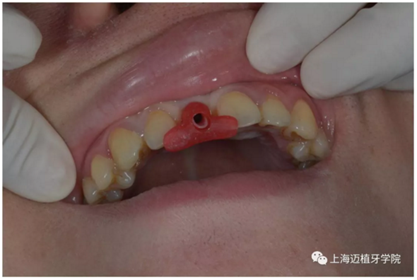

拔除殘根切開翻瓣

植入植體DTS:4.1*10 15A042/0061